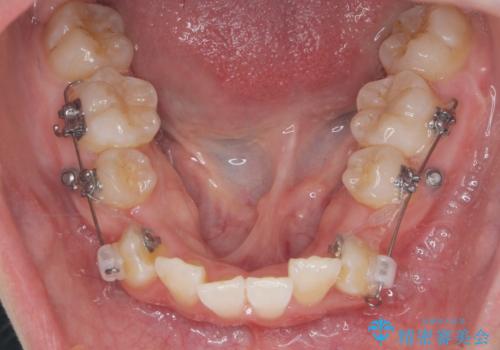

突き出た前歯を治したい 小臼歯抜歯+マルチブラケット矯正

- 矯正装置

- ワイヤー矯正

前歯の角度を改善するために小臼歯4本の抜歯を行いワイヤー マルチブラケットを用いて、しっかりと前歯の角度を改善する治療計画としました。